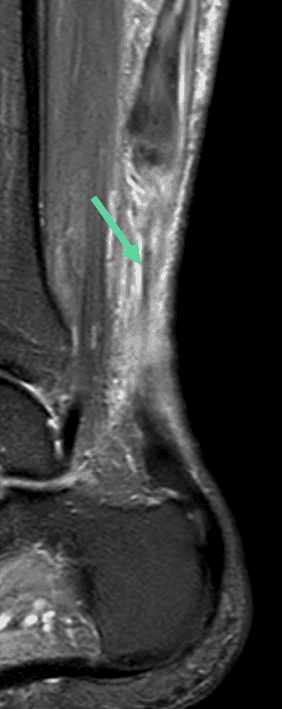

Large solution de continuité tendineuse en lien avec une rupture proximale complète du tenon calcanéen.

Dans ce cas précis, il existe un tendon plantaire grêle (flèches vertes) qui apparaît continu, épargné par la rupture tedineuse, ce cas de figure est parfois interprété à tort comme une rupture partielle du tendon calcanéen.

Sagittal T2 FS